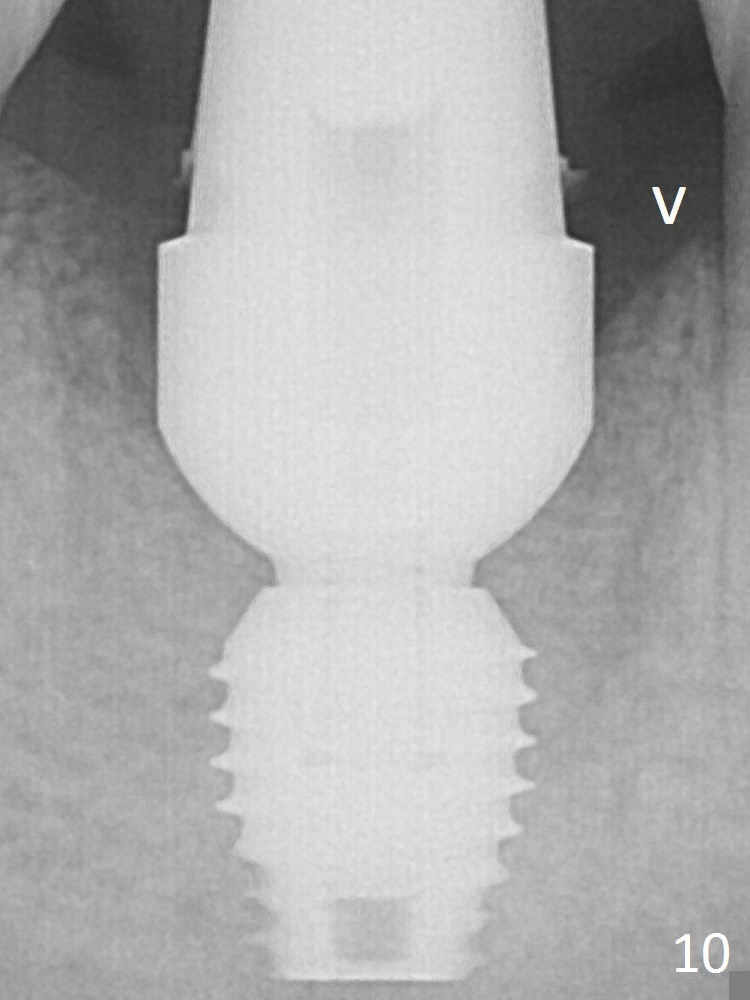

Then bone graft (Fig.7 *) and 7.8x5.5(6) mm abutment are placed.

The bone density around and above (Fig.10 arrowhead) the implant increases 2 months postop.